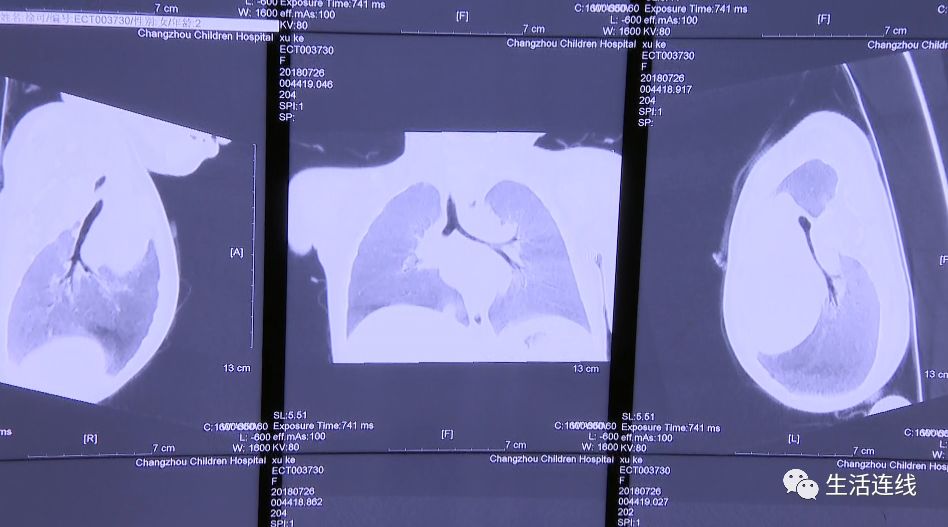

医生了解情况后,怀疑孩子是气道异物引发的肺炎。在做了气管镜检查后,C T显示一团絮状的物体,堵住了孩子的左侧支气管口。为了缓解患儿情况,医生连夜为孩子做了手术,最终取出来几块细碎的黄鳝肉。经过几天的抗炎治疗,贝贝康复出院了。